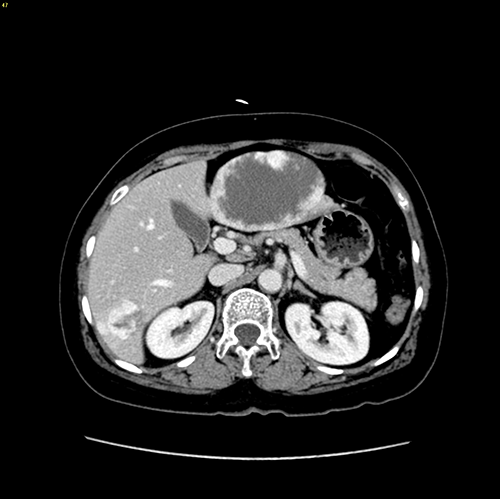

肝血管瘤--左肝外侧叶切除